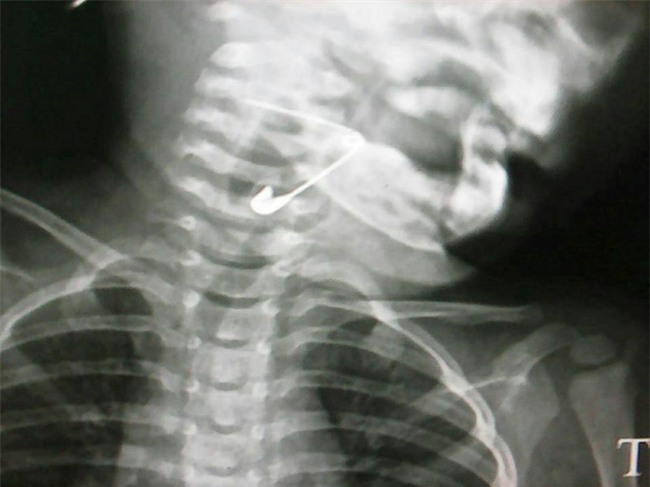

| Chiếc kim băng nằm ở vùng hạ họng thanh quản của bé gái 18 tháng tuổi. Ảnh: Bệnh viện cung cấp. |

Mẹ bệnh nhi cho hay, sáng cùng ngày cháu Vân chơi đùa với người thân thì vô tình nuốt chiếc kim băng đang cài trên ngực áo. Vào viện cấp cứu, bé được chụp phim thì phát hiện chiếc kim ở dạng mở (dài hơn 3 cm) và vướng lại ở vùng hạ họng thanh quản.